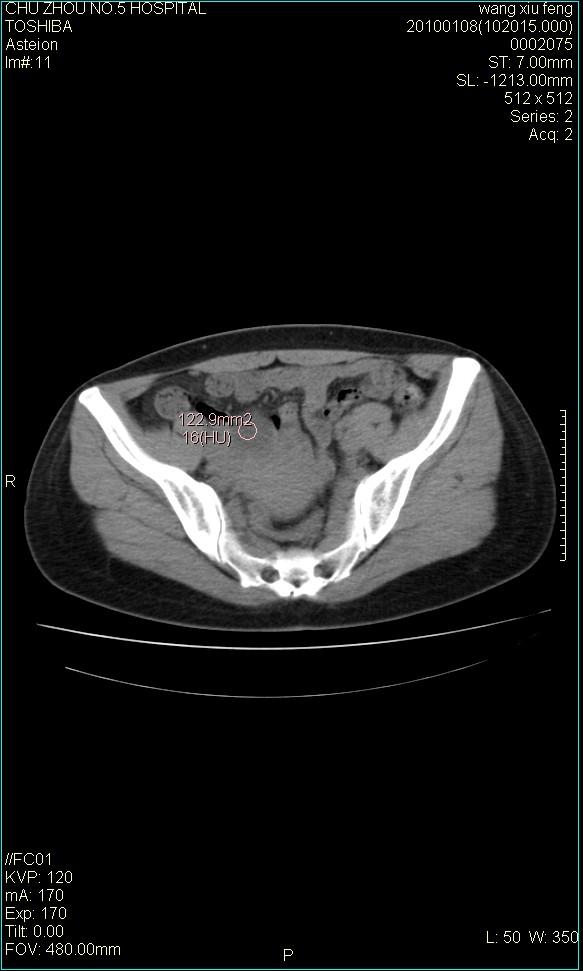

标题: CT24042:子宫右上方囊性包块,性质???? [打印本页]

标题: CT24042:子宫右上方囊性包块,性质????

f-41,左乳腺ca术后4年,b超示:子宫右上方囊性包块约5.5*3.4cm,前日行胸部ct平扫未见明显异常。

囊腺瘤,转移瘤不排除。

考虑右侧卵巢囊腺瘤?

右侧卵巢囊肿或小囊腺瘤。

考虑右侧卵巢囊腺瘤?建议增强!

考虑右侧卵巢囊腺瘤。

考虑右侧卵巢囊性占位性病变(囊肿?囊腺瘤?)。